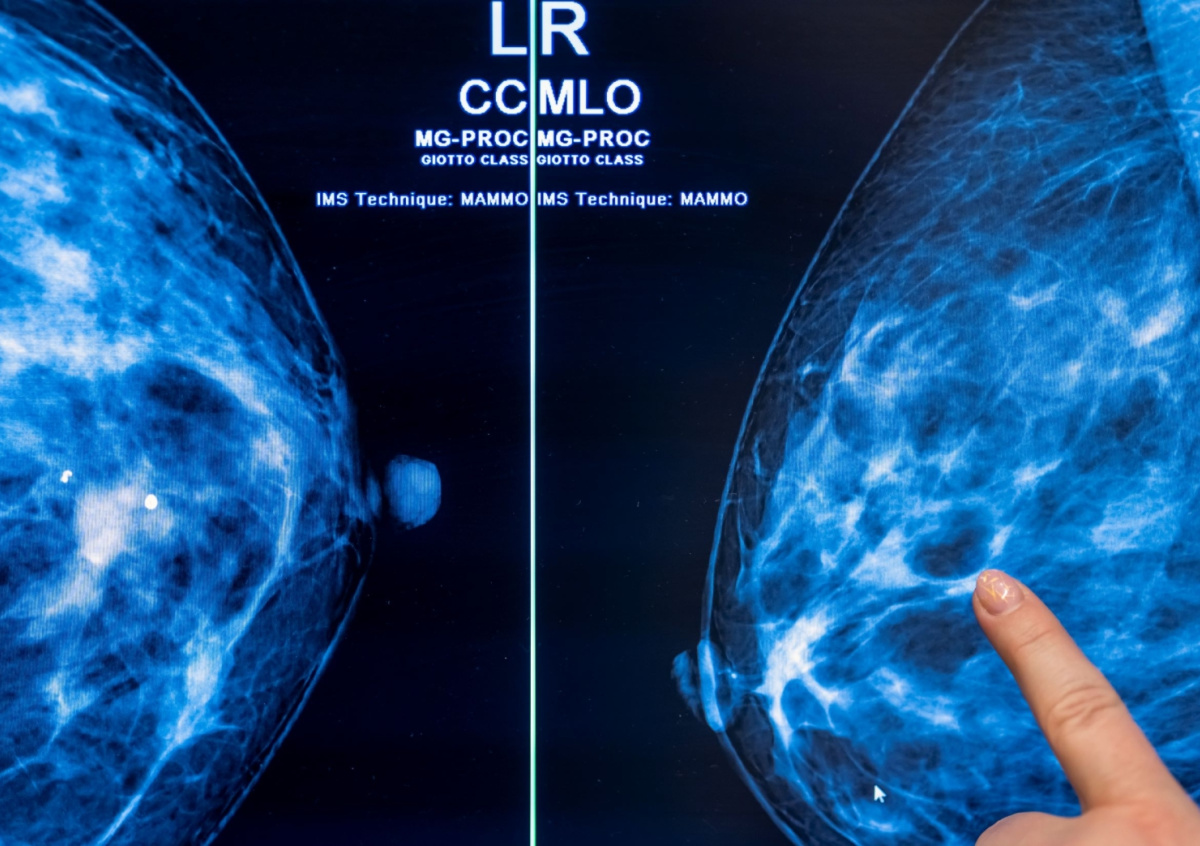

Фото: Michael Hanschke / dpa / Global Look Press

Онколог-маммолог Дмитрий Краcножон заявил, что косвенно на возникновение рака молочной железы (РМЖ) влияет регулярное употребление алкоголя и ожирение. Эксперт при этом отметил, что женские половые гормоны также причастны к возникновению рака, но не являются причиной его появления. По его словам, женщинам после 42 лет желательно выполнять рентгеновское исследование молочных желез, пишут «Известия».